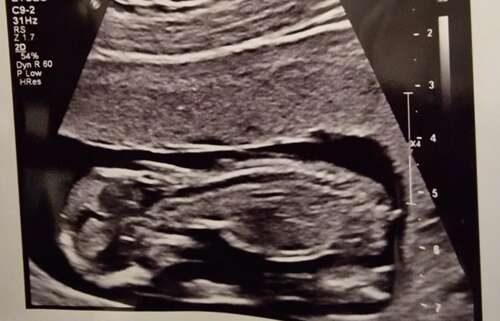

Wat denken jullie? 14 weken

Moet dit een potty shot zijn? Het is in elk geval geen nub foto, zou hem even in het potty shot topic plaatsen

Geen perfect pottyshot, maar ik denk 💙 zo was het bij ons destijds ook